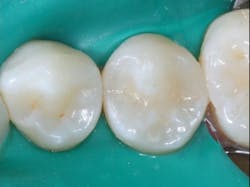

Figures 2a and 2b: Small Class II resin-based composite restorations can often be filled in bulk successfully if the matrix is placed adequately, the light used is powerful enough, and the light is aimed correctly and as close to the resin as possible.

White lines will be minimal or nonexistent when you use the technique described above (figure 3).

Figure 3: The technique described in this article explains how to place resin restorations without producing the well-known "white line" around the margins, as shown in this image.